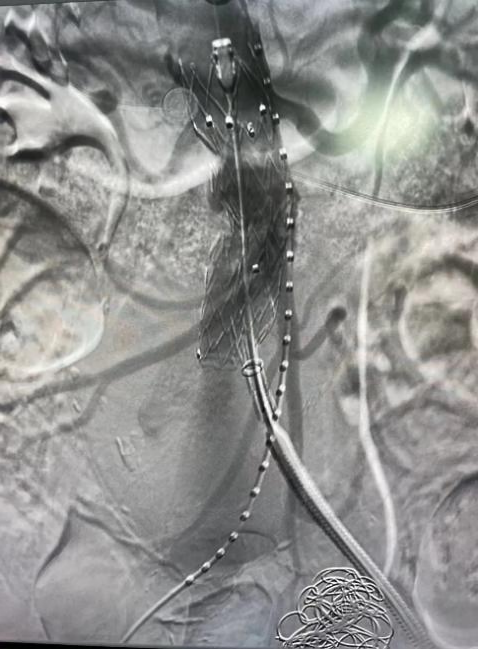

腹主動脈動脈瘤腔內(nèi)隔絕術(shù)

2月28日,神經(jīng)內(nèi)科介入團(tuán)隊在西安交通大學(xué)第一附屬醫(yī)院血管外科蔡惠副主任的指導(dǎo)下成功為李伯實施了“右側(cè)髂動脈瘤栓塞+腹主動脈瘤腔內(nèi)隔絕術(shù)”,手術(shù)歷時2小時順利完成。

術(shù)后造影圖

術(shù)后,李伯再次造影提示支架貼合良好,且未發(fā)現(xiàn)內(nèi)漏、周圍臟器血管閉塞等并發(fā)癥。次日李伯就能下床活動,行走自如。目前,西電集團(tuán)醫(yī)院神經(jīng)內(nèi)科介入團(tuán)隊已成功為四名患者“拆除”腹腔“炸彈”。